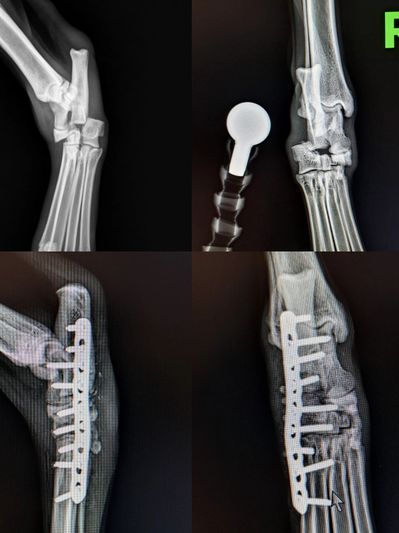

From being hit by a car to suffering a fall, there are multiple reasons your pet may suffer a fractured or broken bone. Many fractures require surgery in order to achieve the best possible outcome.

Surgical repair of fractured bones is priced based on the resources, time and overall anticipated complexity in treating the fracture.

Most fractures will be level 2 fractures even if the bone is broken in multiple places/ pieces/ "shattered"

Fracture level 1 - 2500

Fracture level 2- 3500

Fracture level 3 - 4500

Many of our patients present with multiple fractures. The simultaneous repair of the second and third fracture are generally discounted/ bundled.